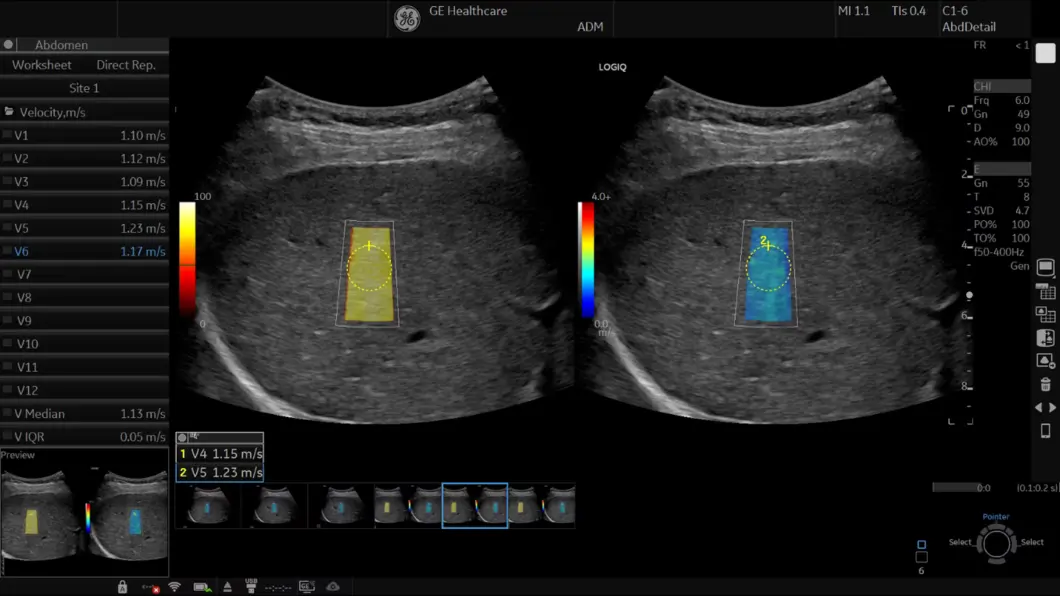

Inteligentne značajke kao što su 2D Shear Wave Elastography, Measure Assistant i Radiantflow™ smanjuju potrebu za invazivnim postupcima pružajući dodatne, vrijedne podatke za informirano donošenje odluka.

2D Shear Wave Elastography omogućuje kvantitativnu procjenu elastičnosti tkiva i pomaže smanjiti potrebu za invazivnim postupcima. Ovaj je alat posebno koristan za dijagnozu i praćenje bolesnika s kroničnom bolešću jetre.

Ultrasound-Guided Attenuation Parameter (UGAP) omogućuje kvantifikaciju steatoze jetre za pomoć u ranoj identifikaciji i praćenju pacijenata s NAFLD, NASH ili ASH.